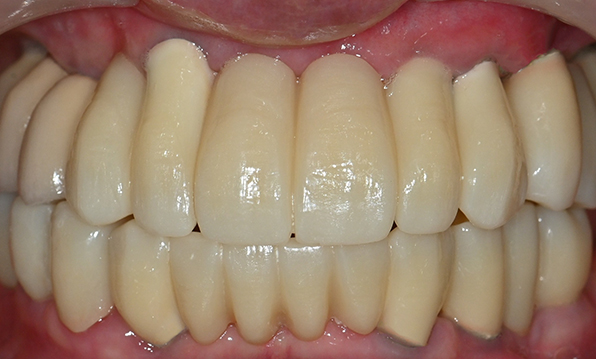

Before & After

Case 01

Before After